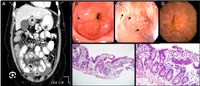

Ảnh đại diện